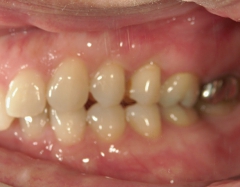

矯正歯科 治療前

36歳女性 磐田市

在住

治療期間2年6

ヶ月